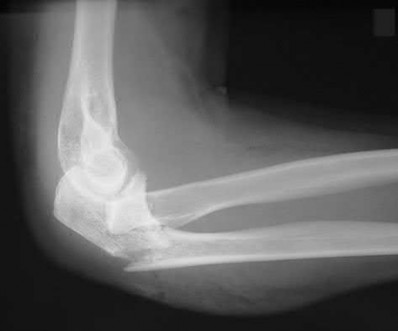

A patient has an elbow injury that includes a coronoid fracture, medial collateral ligament injury, and a radial head fracture. When is excision of the radial head without replacement indicated as definitive treatment for the radial head injury?

Excision is generally not indicated in this clinical scenario Corrent answer: 5

The injury likely represents a terrible triad injury. Restoration of the lateral column is required to restore valgus stability. A repaired or replaced radial head is also thought to be protective of the coronoid fracture repair. Therefore, excision is not indicated. Either radial head arthroplasty or open reduction and internal fixation would be indicated.